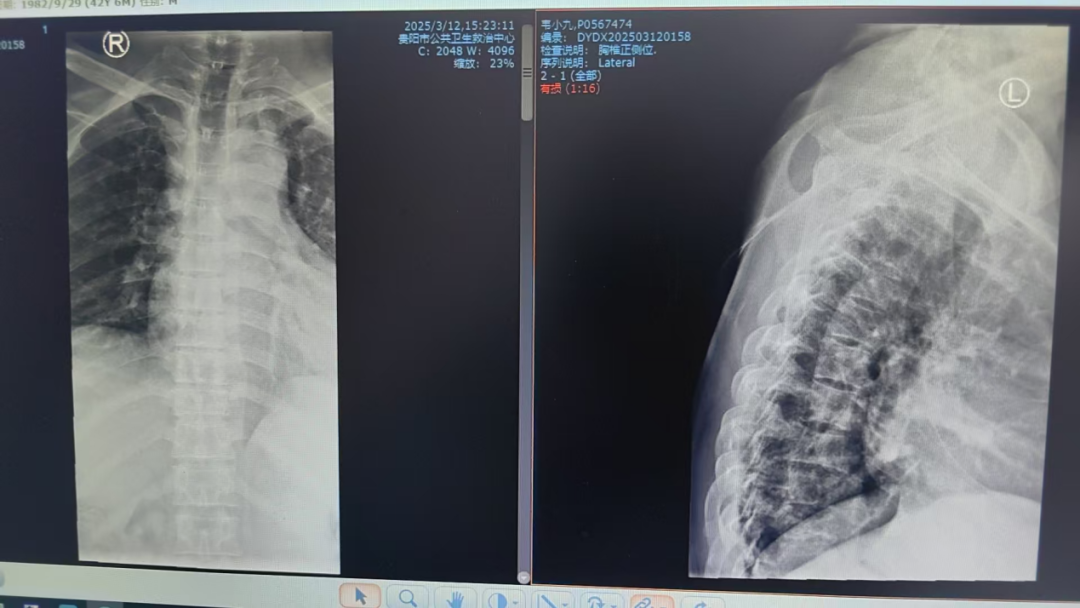

以為是干活勞累,卻突發(fā)癱瘓 “我以為是最近做活路太累了,導(dǎo)致的腰酸背痛,哪曉得突然就癱了!真的感謝周醫(yī)生他們的幫助,把我救回來(lái)了!”談起這番經(jīng)歷,張先生仍心有余悸。 據(jù)悉,今年三月初,42歲的張先生(化名)因胸背疼痛一個(gè)月未進(jìn)行相關(guān)治療,伴隨疼痛進(jìn)行性加重后,入院前3天出現(xiàn)雙下肢無(wú)力、不能行走、大小便失禁等情況。入院時(shí),體查其雙下肢肌力為0,自肋弓以下喪失知覺(jué),無(wú)法坐立,且影像學(xué)檢查顯示,其胸椎上段被結(jié)核性膿腫及壞死骨嚴(yán)重壓迫,脊髓持續(xù)受損。 "每耽誤一分鐘,神經(jīng)壞死風(fēng)險(xiǎn)就增加一分?;颊吣茉僬酒饋?lái)的可能也就減少一分,對(duì)患者家庭是災(zāi)難性后果,我們必須為他爭(zhēng)取時(shí)間。"貴陽(yáng)市公共衛(wèi)生救治中心外三科副主任周波告訴記者;通常情況下,脊柱結(jié)核手術(shù)需2-3周抗結(jié)核治療后再行手術(shù)。但面對(duì)張先生不斷惡化的脊髓損傷,他們必須與患者一同與時(shí)間賽跑:打破常規(guī)的急診手術(shù)決策,進(jìn)過(guò)迅速且嚴(yán)謹(jǐn)?shù)臅?huì)診決策后,靜脈給予一次抗癆治療,團(tuán)隊(duì)當(dāng)機(jī)立斷采用"脊柱前后路聯(lián)合"急診手術(shù)為張先生進(jìn)行施救。“我們首先從前路開胸,清除椎體前方膿腫及壞死組織,植入鈦網(wǎng)替代部分椎體功能,由于椎體跳躍性骨質(zhì)破壞,前路固定不牢固,立即行后路手術(shù),通過(guò)椎弓根釘棒系統(tǒng)實(shí)現(xiàn)脊柱三維穩(wěn)定,再次行后路減壓,雙路徑手術(shù)一次性徹底清除病灶,減壓更充分,復(fù)發(fā)幾率更小。 患者術(shù)前X片 患者胸部CT 患者胸椎核磁共振 術(shù)后復(fù)查的X線 該患者在術(shù)后第一天身體感知覺(jué)有較明顯恢復(fù),第5天開始腳趾恢復(fù)活動(dòng),兩周時(shí)肌力恢復(fù)至3級(jí)以上,截至昨日記者在現(xiàn)場(chǎng)目睹,雙腿已經(jīng)可以自主抬放。周波副主任表示,急性脊髓損傷的黃金救治窗口極短,聯(lián)合入路既能快速減壓又確保長(zhǎng)期穩(wěn)定性,這是恢復(fù)超預(yù)期的關(guān)鍵。預(yù)計(jì)一個(gè)月左右,這位患者就能重新自主行走了。 本次手術(shù)團(tuán)隊(duì)的幾位醫(yī)生正在叮囑患者出院后的注意事項(xiàng) 左起:羅善鵬,石頭,周波,左樂(lè) 專家提示: 腰痛≠腰椎勞損 這些信號(hào)要警惕 針對(duì)近年多發(fā)的"腰痛誤診"現(xiàn)象,周主任特別提醒:腰椎結(jié)核多以持續(xù)性腰痛為主,多伴低熱、盜汗、體重下降等結(jié)核中毒癥狀;而腰椎間盤突出典型表現(xiàn)為腿痛腿麻等。一定要注意的是當(dāng)出現(xiàn)腰痛合并下肢無(wú)力、大小便功能障礙時(shí),無(wú)論屬于哪一種情況都需立即就醫(yī)。 據(jù)統(tǒng)計(jì),我國(guó)結(jié)核感染人群超2億,其中5%-10%的肺外結(jié)核可累及脊柱。專家強(qiáng)調(diào),骨結(jié)核雖發(fā)病率低,但致殘率高,早期規(guī)范治療可避免災(zāi)難性后果。 專家簡(jiǎn)介 周波,男,43歲,副主任醫(yī)師,中國(guó)抗癆協(xié)會(huì)結(jié)核病健康促進(jìn)分會(huì)委員,中華醫(yī)學(xué)會(huì)貴陽(yáng)市骨科分會(huì)委員、貴陽(yáng)市康復(fù)醫(yī)學(xué)會(huì)委員,貴陽(yáng)市骨科質(zhì)量委員會(huì)委員,貴陽(yáng)市艾滋病性病防治協(xié)會(huì)委員,中國(guó)中醫(yī)藥信息學(xué)會(huì)骨科分會(huì)委員,從事臨床醫(yī)學(xué)骨外科專業(yè)15余年,擅長(zhǎng)脊柱結(jié)核及其截癱患者的治療,搶救脊髓功能,擅長(zhǎng)骨與關(guān)節(jié)結(jié)核的診治,髖、膝關(guān)節(jié)置換的治療,術(shù)后療效顯著,有效減少患者的致殘率。在國(guó)內(nèi)學(xué)術(shù)核心雜志發(fā)表學(xué)術(shù)專業(yè)文章15篇。